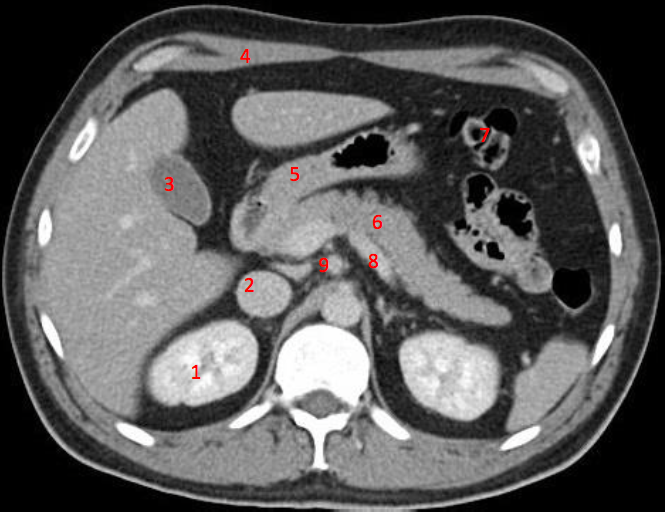

1

Number 3?

IVC

2

Number 1?

R Kidney

3

4

How well did you know this?

Not at all